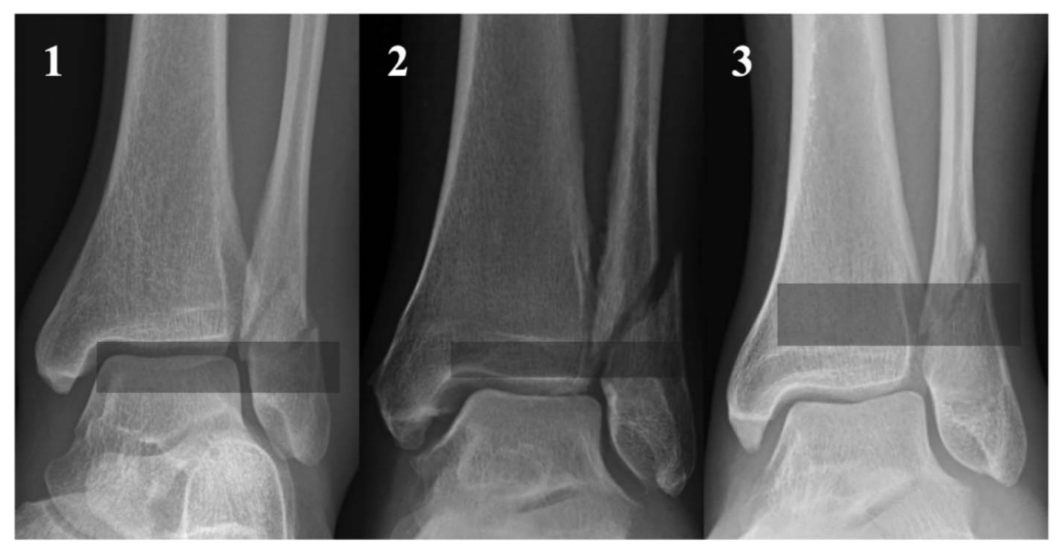

图2Danis-Weber B型骨折,根据近端骨折块最远端位置分区。1区定义为骨折块最远端位于胫骨远端关节面平面以下;2区为位于胫骨远端骺线闭合瘢痕与远端关节面之间;3区为骺线闭合瘢痕以上。

图3 分区示意图。